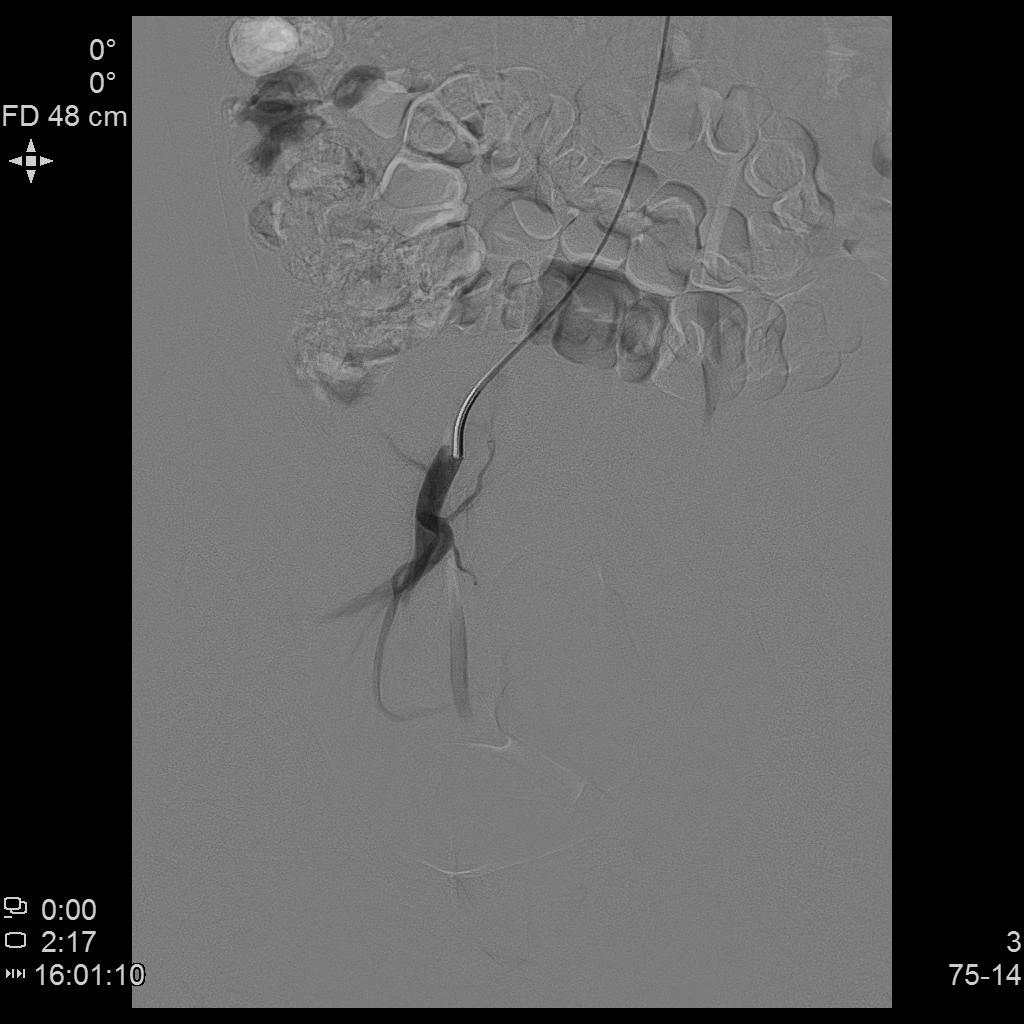

- DSA下行双侧子宫动脉栓塞治疗。

左侧子宫动脉造影

右侧子宫动脉造影

- 经桡动脉入路置入导管造影显示双侧子宫动脉明显增粗,染色丰富,子宫明显增大。

- 微导管进一步超选插管右侧子宫动脉主干造影确认位置。

- 微导管进一步超选插管左侧子宫动脉主干造影确认位置。